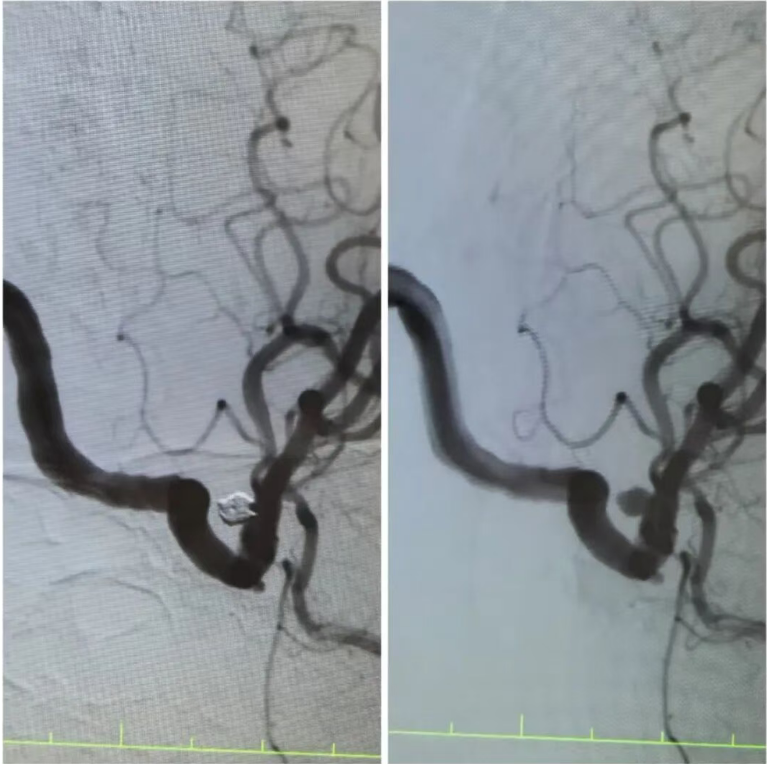

在王阿姨的造影檢查上,可清晰地看到動(dòng)脈瘤的形態(tài):如同血管上懸掛的“小囊袋”,薄如蟬翼的瘤壁隨時(shí)可能再次破裂。“開(kāi)顱手術(shù)創(chuàng)傷大,老人基礎(chǔ)疾病多,風(fēng)險(xiǎn)極高,而介入栓塞術(shù),能通過(guò)股動(dòng)脈穿刺的“鑰匙孔”路徑,精準(zhǔn)封堵動(dòng)脈瘤?!笔中g(shù)團(tuán)隊(duì)反復(fù)推演方案,最終選定顱內(nèi)動(dòng)脈瘤栓塞術(shù)——用纖細(xì)的微導(dǎo)管將彈簧圈送入動(dòng)脈瘤腔內(nèi),像“織網(wǎng)”一樣填充瘤腔,隔絕血流沖擊,從根源上消除破裂風(fēng)險(xiǎn)。

手術(shù)臺(tái)上,丁院長(zhǎng)握著導(dǎo)管在血管中精準(zhǔn)穿梭,如同在迷宮中尋找唯一的出口。當(dāng)微彈簧圈依次填入動(dòng)脈瘤,造影顯示瘤腔被完美“封堵”,載瘤動(dòng)脈血流恢復(fù)通暢,這枚困擾老人許久的“炸彈”,終于被安全拆除。術(shù)后的王阿姨頭暈頭痛癥狀消失,胸悶氣短的老毛病也因身心狀態(tài)改善而減輕?!案杏X(jué)腦袋里的‘炸彈’沒(méi)了,整個(gè)人都輕快了!”